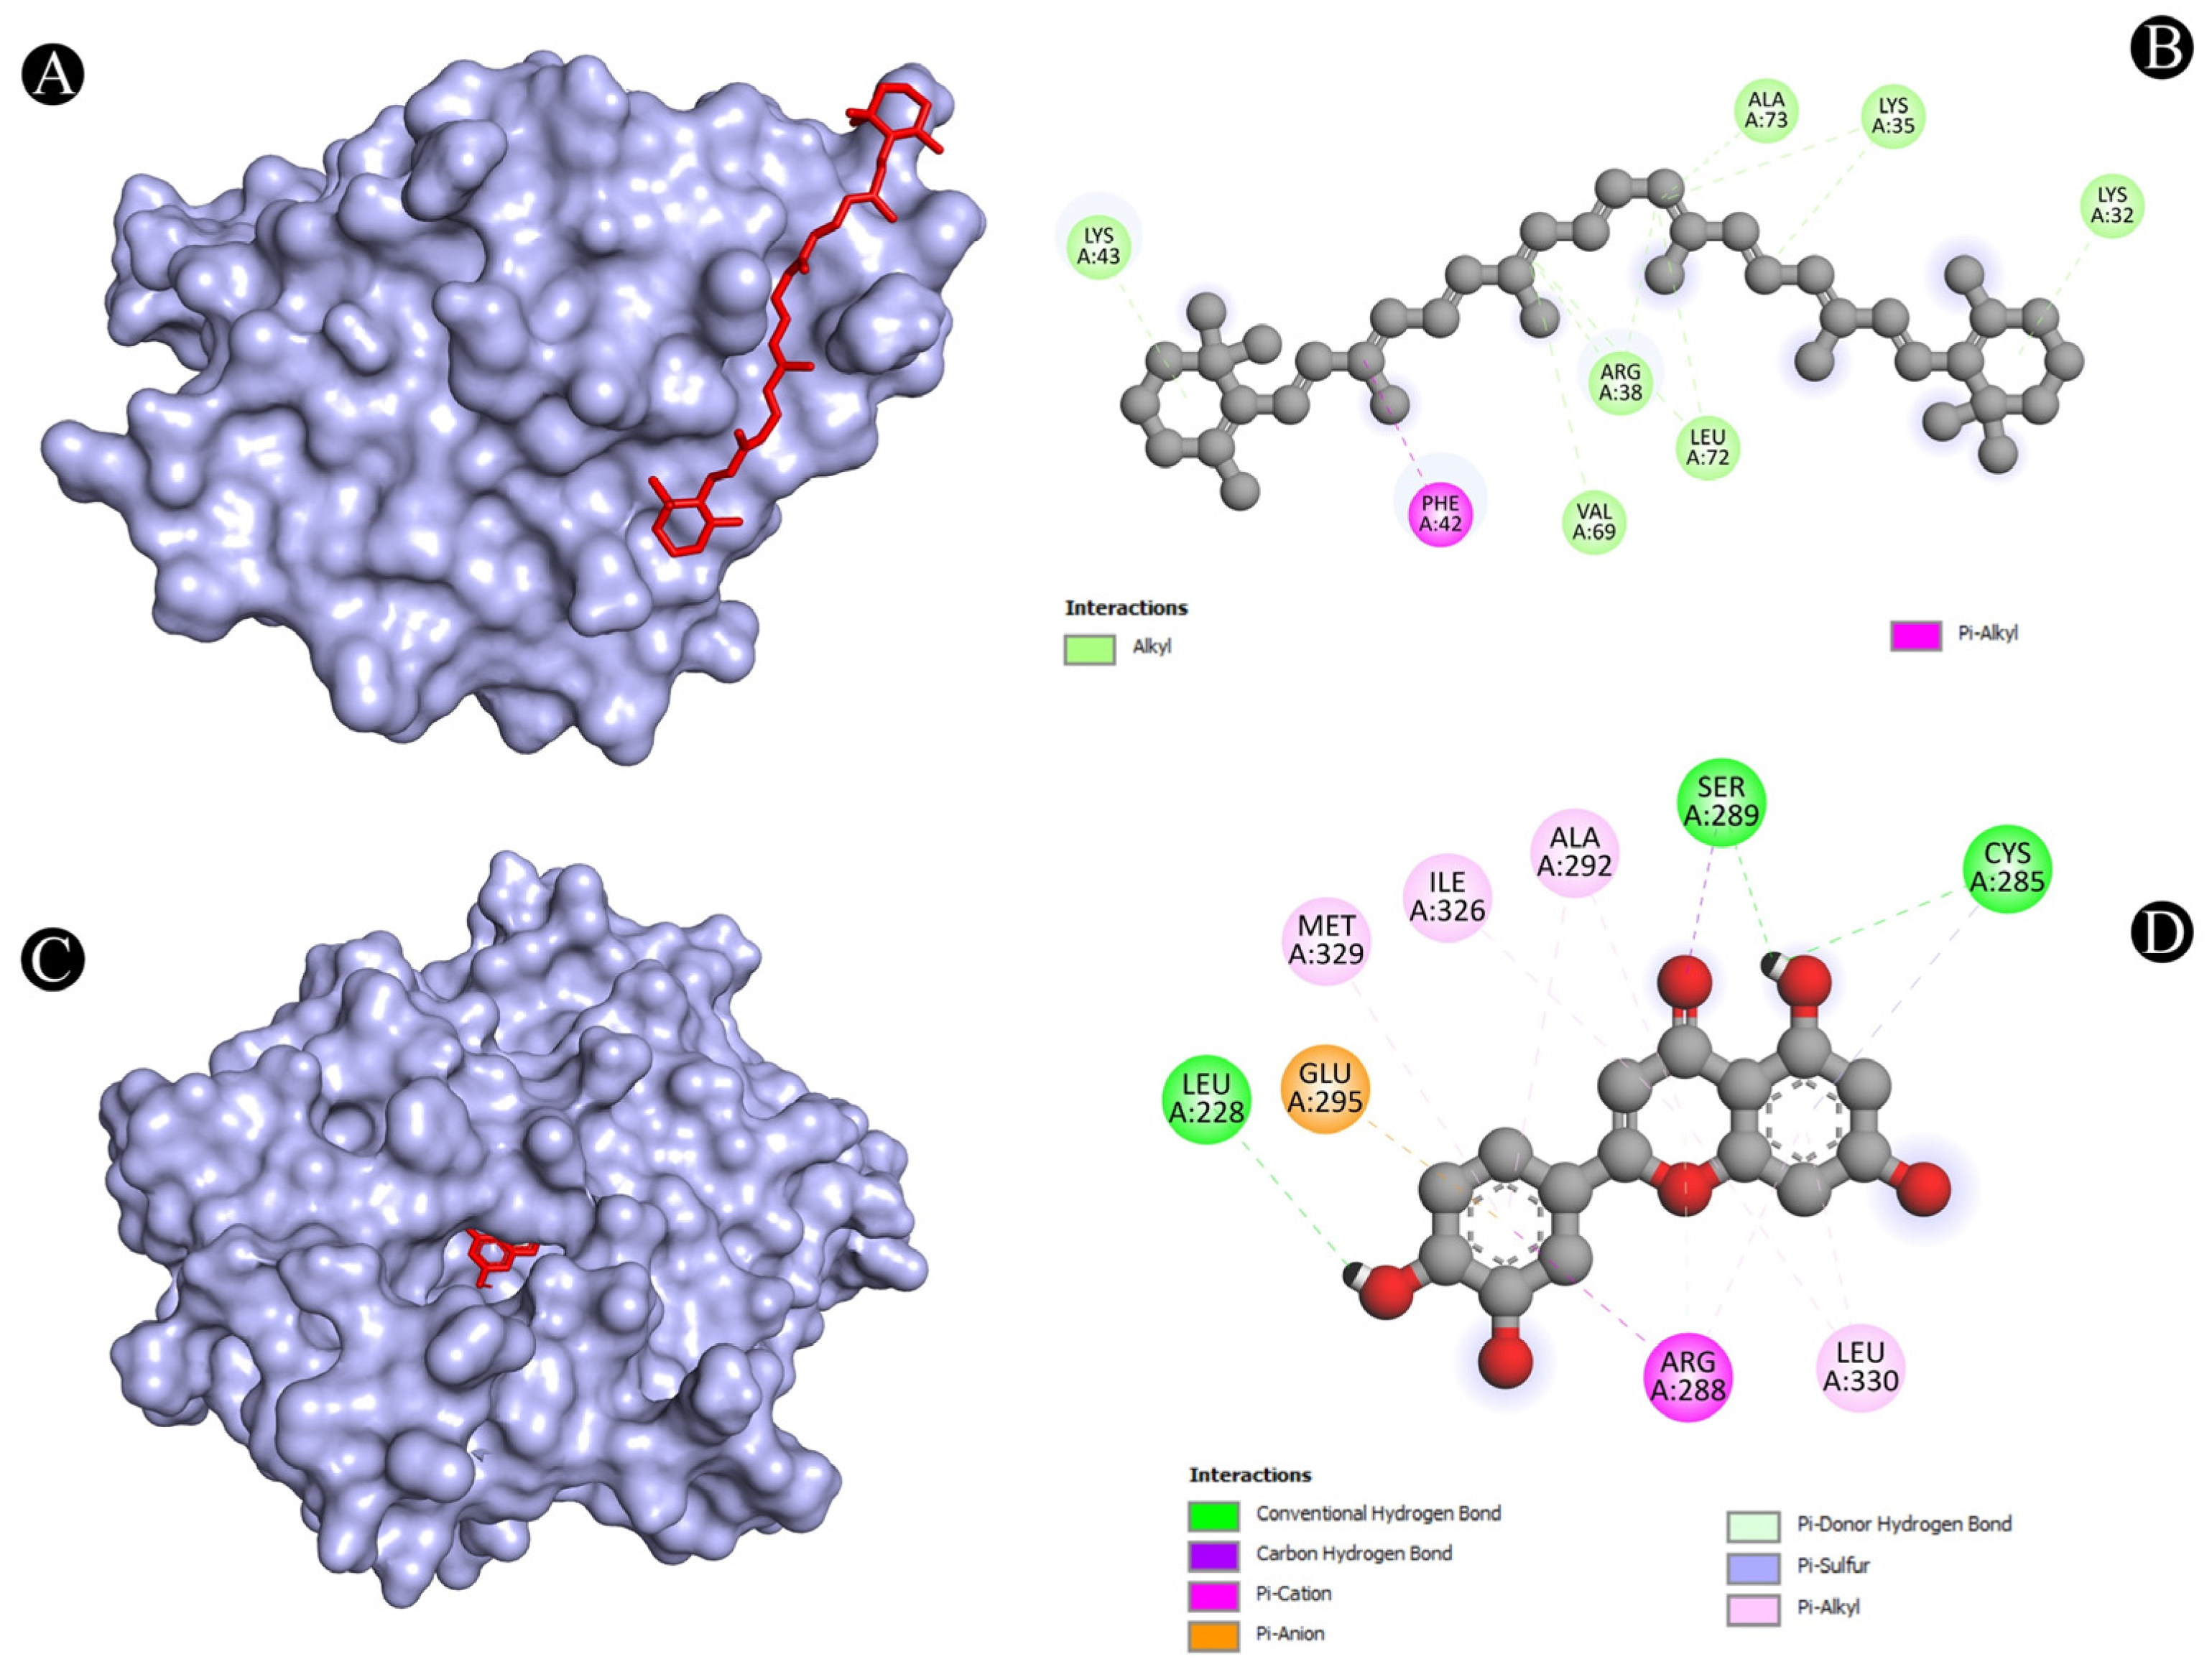

3.4. Molecular Docking Analysis